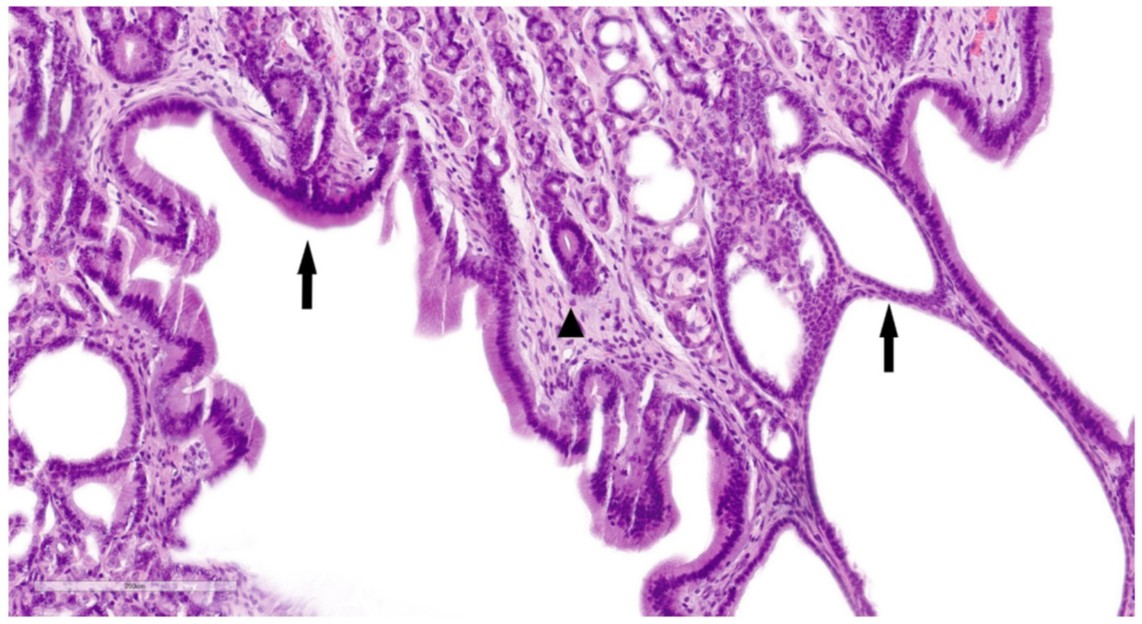

↑ 囊性黏膜腺体由扁平至低立方上皮细胞排列(箭头)。在黏膜固有层可见轻度淋巴浆细胞性炎症浸润(三角形)。

黏膜固有层多灶性轻度扩张,少量淋巴细胞、少量浆细胞和罕见中性粒细胞,伴有多灶性轻度浅表黏膜纤维化。黏膜下层显示轻度水肿和充血。肌层无异常。肠系膜淋巴结显示轻度淋巴滤泡增生。所有发现均与囊性腺体扩张的增生性纤维化胃病一致,类似于犬Ménétrier病。